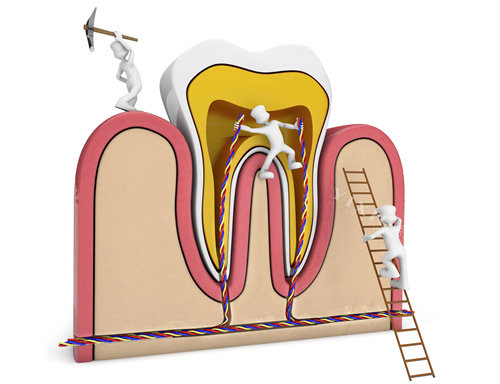

“凌晨两点牙疼到哭,直接打车冲到浙大口腔!”市民林女士回忆道,“急诊医生检查后说是急性牙髓炎,立刻做了开髓引流,疼了半小时就缓解了!”

作为浙江省口腔医疗的“顶梁柱”,浙大口腔的急诊科全年无休,24小时接诊。无论是牙齿断裂、剧烈疼痛,还是颌面部外伤出血,这里都能快速处理。医院位于拱墅区武林路,夜间急诊通道畅通,标识清晰,即使深夜也能快速找到。